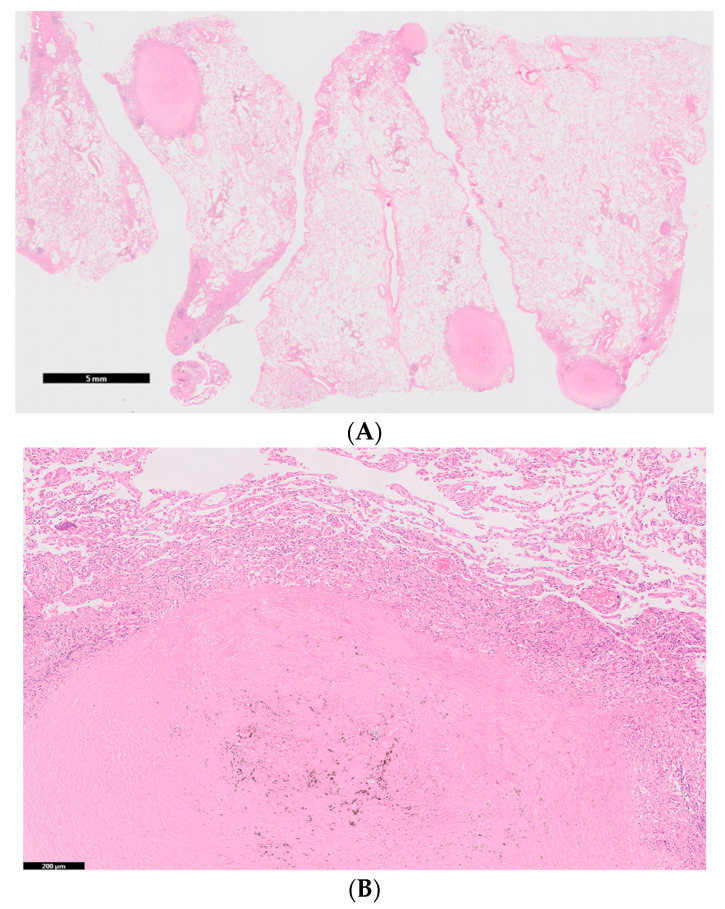

Positron emission tomography showed no significant accumulation on the nodules. No extrathoracic manifestations were observed, both clinically and radiologically. The pulmonary function test results revealed the following: total lung capacity, 4.14 L (116.3% of the predicted value); forced vital capacity, 4.00 L (112.4% of the predicted value); forced expiratory volume in 1 s, 3.16 L (109.0% of the predicted value); and carbon monoxide diffusion capacity of the lung, 6.55 mL/min/mm Hg (88.2% of the predicted value). An analysis of the bronchoalveolar lavage fluid obtained from the middle lobe (right B5) showed 2.4 × 105 cells/mL (88.9% macrophages, 9.9% lymphocytes, 1.0% neutrophils, and 0.0% eosinophils), with a CD4/CD8 ratio of 0.7. Lung specimens from the anterior basal segment of the right lower lobe, obtained by transbronchial lung biopsy, exhibited non-necrotizing granulomatous inflammation and chronic multinucleated giant cells with marked dust deposition. To confirm the diagnosis, lung specimens from the lateral segment of the right middle lobe and anterior basal segment of the right lower lobe were obtained via video-assisted thoracoscopic surgery. The specimens showed 5–12 mm silicotic nodules with dust deposition (silica- and berlin blue staining-positive dust), surrounded by fibrotic changes and macrophages on the pleura and around the airways (Figure 3A,B). Hemosiderin-laden macrophages were observed in the surrounding alveoli of the nodules. Several non-necrotizing granulomas along the lymphatic routes were also observed (Figure 3C,D). No asbestos bodies were observed, and immunostaining for Cutibacterium acnes, Ziehl–Neelsen staining, and Grocott staining were all negative.